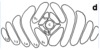

Safe zone for occipital screw placement

Triangular region created by connecting 2 dots 2cm lateral to the external occipital protuberance, and a point 2 cm inferior to it

Point B on the pictures

Safe zone for halo application (anterior pins)?

Lateral 1/3 of eyebrow, below the equator (site D in figure)

Avoids supraorbital and supratrochlear nerves